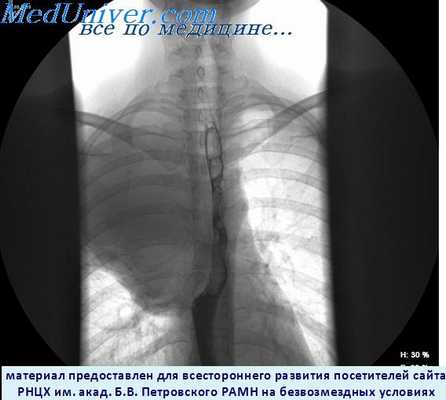

Схематическое изображение

пищевода. 1 – глотка, 2 – верхнее

сужение пищевода, 3 – шейный

отдел пищевода, 4 – аортальное

сужение пищевода, 5 – грудной

отдел пищевода, 6 – диафрагмальное

сужение пищевода, 7 – диафрагма,

8 – кардиальный отдел желудка,

9 – брюшной отдел пищевода

(Шишко В.И., Петрулевич Ю.Я.)